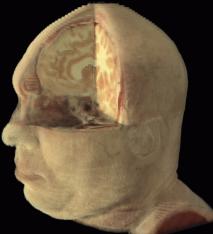

La ricostruzione per superfici, mostrata in figura 1‑5, considera solamente i dati relativi alla superficie dell’oggetto, ignorandone la struttura. Una volta definito il profilo di interesse per ogni sezione, i dati residui possono essere eliminati. L'oggetto può quindi essere rappresen­tato come una sequenza di curve approssimanti (dette spline) impilate nello spazio, connesse da un mosaico di poligoni (usual­mente triangoli) o intercettate da una superficie complessa.

Figura 15 Ricostruzione per superfici